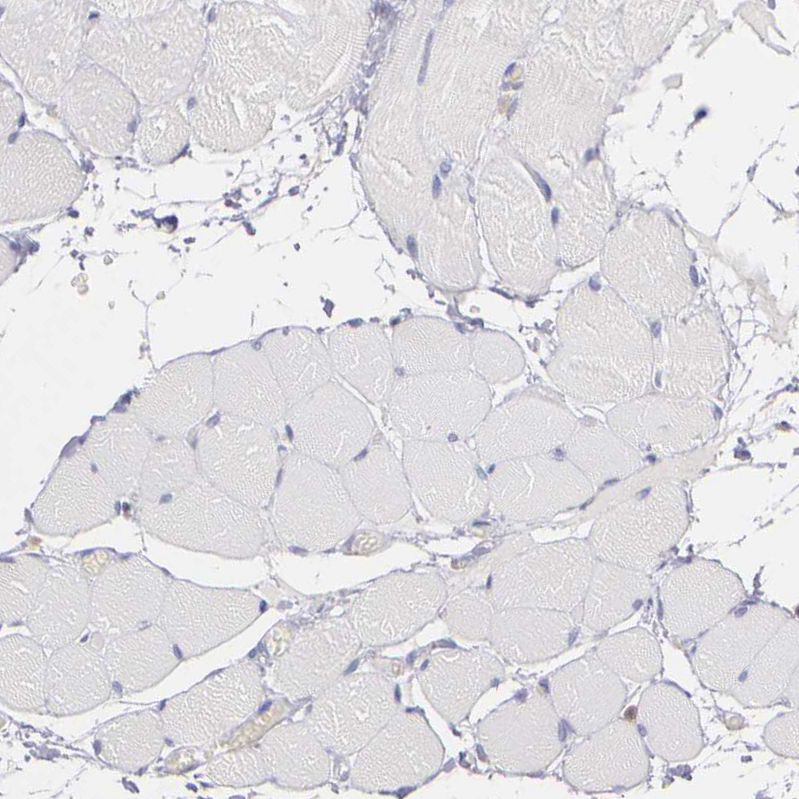

Immunohistochemistry analysis in human tonsil and skeletal muscle tissues using HPA001890 antibody. Corresponding PRKCD RNA-seq data are presented for the same tissues.